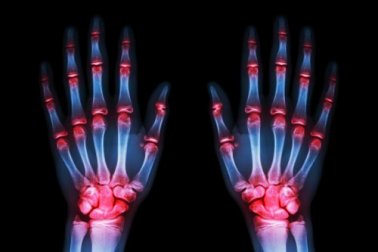

A artrose afeta a 52% das mulheres, frente a 29% dos homens. Costuma dar as primeiras pistas entre os 54 e os 60 anos e, em geral, segue este mesmo padrão:

- A artrose é mais comum nas mãos (70% dos casos).